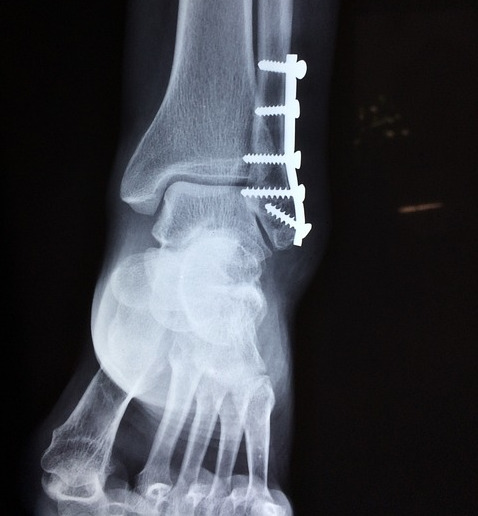

Fracturas

Tratamos todo tipo de fracturas, con procedimientos actualizados, con el objetivo de que el paciente logre recuperar su mobilidad.

También atendemos a los pacientes que tienen algún padecimiento derivado de alguna fractura tales como: retardo en consolidación del hueso, mala alineación o alguna secuela.

- Hizo una rotación en el Hospital Universtario de Bellvitge en Barcelona, enfocándose en cirugías de pie, tobillo y reconstruncción articular. (2012).